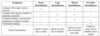

Renal Cell Carcinoma

Clear Cell RCC

Clear Cell RCC

Papillary RCC

Papillary RCC

Chromophobe RCC